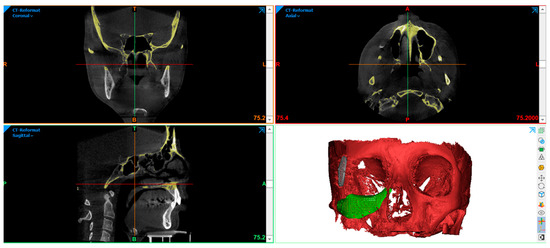

2.4. Virtual Planning of Patients-Specific Implants

2.5. Manufacturing of Patient-Specific Implants and Surgical Procedure